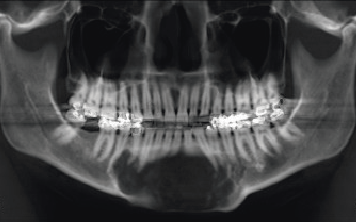

Es la rama de la odontología encargada del diagnóstico y tratamiento quirúrgico de las alteraciones en los tejidos duros y blandos de la boca como patologías infecciosas, tumorales y de malformaciones bucales y maxilofaciales, utilizando como ayudas diagnósticas la imagenología, la histopatología y pruebas de laboratorio clínico.

El odontólogo especialista en esta área posee el conocimiento y la destreza para toma de biopsias, realización de tratamientos de urgencias, manejo de alteraciones de la boca como: frenillos traccionantes, dientes retenidos o incluidos, cirugías pre protésicas, cirugías maxilo facilaes y reconstructivas.